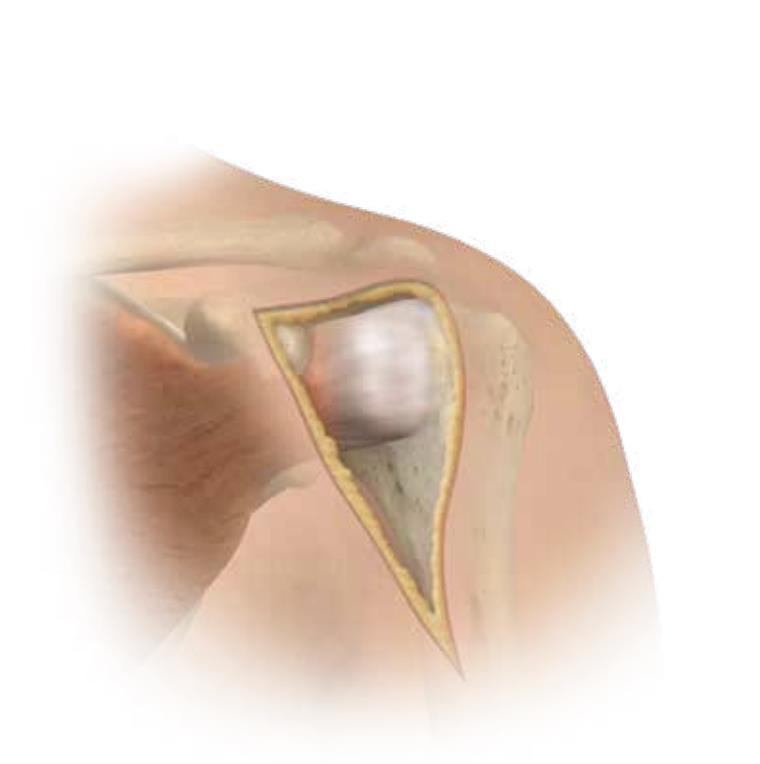

Summary The OsseoFit™ Stemless Shoulder System is indicated for anatomic total shoulder arthroplasty in patients where a bone-sparing, stemless solution is desired to maximize humeral fixation. It achieves this through OsseoTi® Porous Metal Technology and a site-specific fin design that creates a stable, biological press-fit while simplifying the surgical workflow with integrated suture holes. This system addresses a wide variety of patient anatomies using its versatile inlay and onlay size options. Indications Indications osteoarthritis indicated for anatomic total shoulder applications Contraindications local/systemic infection, sepsis, and osteomyelitis active local or systemic infection sepsis osteomyelitis inadequate humeral bone inadequate bone may lead to poor implant fixation large metaphyseal cysts may compromise stemless fixation irreparable cuff tear rotator cuff must be functionally reconstructable for anatomic total shoulder arthroplasty revision of any stemmed or stemless prothesis contraindicated for revision of any stemmed or stemless prosthesis Anatomy Osteology humeral head anatomic neck greater tuberosity lesser tuberosity bicipital groove metaphyseal cancellous bone Muscles deltoid forms the lateral border of the deltopectoral interval pectoralis major forms the medial border of the deltopectoral interval subscapularis released and repaired according to surgeon preference Ligaments glenohumeral capsule is released as needed to expose the humeral head and glenoid coracohumeral ligament contributes to rotator interval constraint superior, middle, and inferior glenohumeral ligaments contribute to anterior stability transverse humeral ligament overlies the bicipital groove Nerves axillary nerve courses inferior to the subscapularis and around the lateral humerus must be protected musculocutaneous nerve lies medial to the coracobrachialis and conjoint tendon suprascapular nerve is at risk with aggressive posterior-superior glenoid exposure Blood supply anterior and posterior humeral circumflex arteries arcuate artery is a terminal branch of the anterior humeral circumflex system suprascapular and circumflex scapular vessels Preoperative Planning X-rays A/P, scapular Y and axillary views evaluate bony anatomy, humeral head position, glenoid wear, deformity, and acquired bone loss use x-ray templates to estimate stemless humeral implant size assess whether an anatomic total shoulder reconstruction is appropriate CT assess bone quality and identify any humeral bone tissues use to assess bone quality and identify humeral bone issues that may affect implant selection evaluate metaphyseal bone stock, cysts, avascular necrosis, deformity, and cortical support Approach Extended deltopectoral anterior incision with an optional biceps tenodesis beginning immediately above the coracoid process and extending distally and laterally, following deltopectoral groove along the anterior border of the deltoid Technique Humeral head resection expose the humeral head and identify anatomic neck landmarks fixed-angle resection targets 135° inclination and 30° retroversion select left- or right-specific extramedullary resection guide align the guide post with the humeral shaft for fixed-angle resection align the 30° version rod with the forearm flexed at 90° place pins to define version and inclination and to stabilize the cutting surface resect the humeral head through the far side of the humeral head adjust the resection with the guide or calcar planer if needed assess bone quality with direct pressure perpendicular to the resected surface consider stemmed humeral fixation if cancellous bone is easily depressed or primary stability is questionable Humeral protection during glenoid preparation select the humeral resection cover that most closely fits the resected surface prepare the glenoid using the appropriate compatible glenoid technique remove the humeral resection cover before humeral sizing Humeral sizing place the humeral sizer onto the resection surface select the size intended to optimize cancellous bone fixation without violating the inner cortical rim orient the sizer so the bicipital groove bisects the superior and anterior fins insert the central Steinmann pin through the center of the sizer and through the lateral cortex avoid deep lateral cortical penetration to reduce risk to the axillary nerve place a lateral humeral retractor as needed to protect the axillary nerve confirm sizing after any additional planing Humeral bone preparation (boss reaming) ream until the boss reamer bottoms out on the resected surface ream over the central Steinmann pin with the boss reamer protect the lateral humerus and axillary nerve with a retractor remove the boss reamer while leaving the central Steinmann pin in place Humeral bone preparation (broaching) select the reference foot based on implant size select the broach that corresponds to the humeral sizer align the broach superior fin with the superior indicator line on the broach inserter slide the assembly over the central Steinmann pin until the broach contacts the resection surface remove the inserter-reference foot assembly and central Steinmann pin perform broach stability testing consider stemmed humeral fixation if the broach is unstable Humeral head trialing determine humeral head diameter and height using the humeral head sizing template or the resected humeral head seat the head trial assembly into the broach rotate the trial assembly with the hex driver to assess coverage of the resection surface confirm alignment with the anterior and posterior borders of the humeral resection increase offset if the head trial does not cover one side of the resection decrease offset if the head trial overhangs the resected bone reduce the joint and perform trial range of motion record the final offset letter or interval on the proximal humerus remove and disassemble the head trial assembly Implant insertion remove the broach with the slap hammer while maintaining an on-axis trajectory use the same reference foot size used for broach insertion select the implant size corresponding to the final broach and operative side slide the reference foot down until it uniformly contacts the resection surface confirm superior fin markings on reference foot, implant, and bone are aligned disengage the inserter-reference foot assembly with axial traction and slight rotational force as needed onlay implant center boss is slightly proud of the resection surface, with fin top surfaces flush inlay implant sits below the resection surface Humeral head implantation select the final humeral head implant matching the trial diameter and height use the offset letter or interval determined during trialing place the humeral head into the concave surface of the impactor base on a rigid sterile table impact the adapter into the humeral head with the disposable impactor using a mallet, strike the head impactor at least twice until the humeral head is flush with the resection visually confirm uniform seating consider implant subsidence and stemmed fixation if no pre-impaction gap is present Technical specifications Implant design anatomically shaped asymmetric anchor design designed to match natural asymmetric humeral anatomy designed to maximize cancellous bone fit and help avoid cortical impingement six-fin configuration with progressive tapered wedge design fins are designed for press-fit insertion each fin contains a fully porous window anterior suture holes are present for subscapularis repair Porous technology OsseoTi® Porous Metal Technology is used in the stemless implant porous architecture is designed to mimic human cancellous bone design incorporates a fully porous 3D printed OsseoTi® lattice within a titanium framework Technical specifications OsseoFit Onlay Anchor Implant Side Size Left 1, 2, 3, 4, 5 Right 1, 2, 3, 4, 5 OsseoFit Inlay Anchor Implant Side Size Left 1, 2, 3, 4, 5 Right 1, 2, 3, 4, 5 OsseoFit Humeral Head Adapter